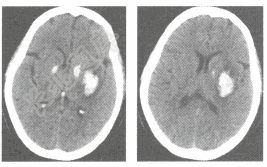

- 单项选择题女,68岁,突发右侧肢体轻度偏瘫,高血压病史多年,平扫CT检查如图,最可能的诊断是

A、脑炎

B、脑出血

C、脑脓肿

D、脑梗死

E、胶质瘤